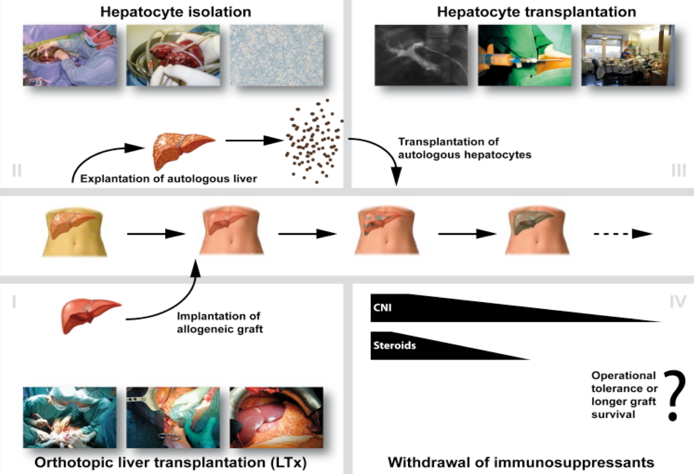

Once these cells have engrafted, it is postulated that the autologous cells will repopulate the allogeneic graft liver as they have a selective advantage over the donor tissue due to their autologous origin. It is hypothesized that this will lead to a neo-hybrid liver graft, reducing the need for immunosuppression and possibly inducing tolerance to both the entire engrafted tissue and the allogeneic donor matrix.

Once these cells have engrafted, it is assumed that autologous cells will repopulate the allogeneic liver, since they should have a selective advantage due to their autologous origin. It is postulated that this will lead to a neo-hybrid liver graft, reducing immunogenicity and inducing immunoregulation thus minimizing the need for extensive immunosuppression and eventually inducing operational tolerance.

The tolerogenic potential of transferred autologous liver cells will be investigated in a rat liver transplant model. In this model, post-transplant immunosuppressive therapy will be based on calcineurin inhibitors (CNI). Immunosuppressive protocols based on CNI are clinically used for LTx and seem appropriate for liver cell transplant studies since these substances do not perturb transplanted hepatocytes. The effects of weaning of immunosuppression will be investigated in this small animal model. Additionally, the tolerogenic potential of autologous liver cells will be further challenged by generating a pre-transplant donor-reactive memory in the recipient, as memory T and B cells represent a major barrier for long-term graft function in clinical transplantation.